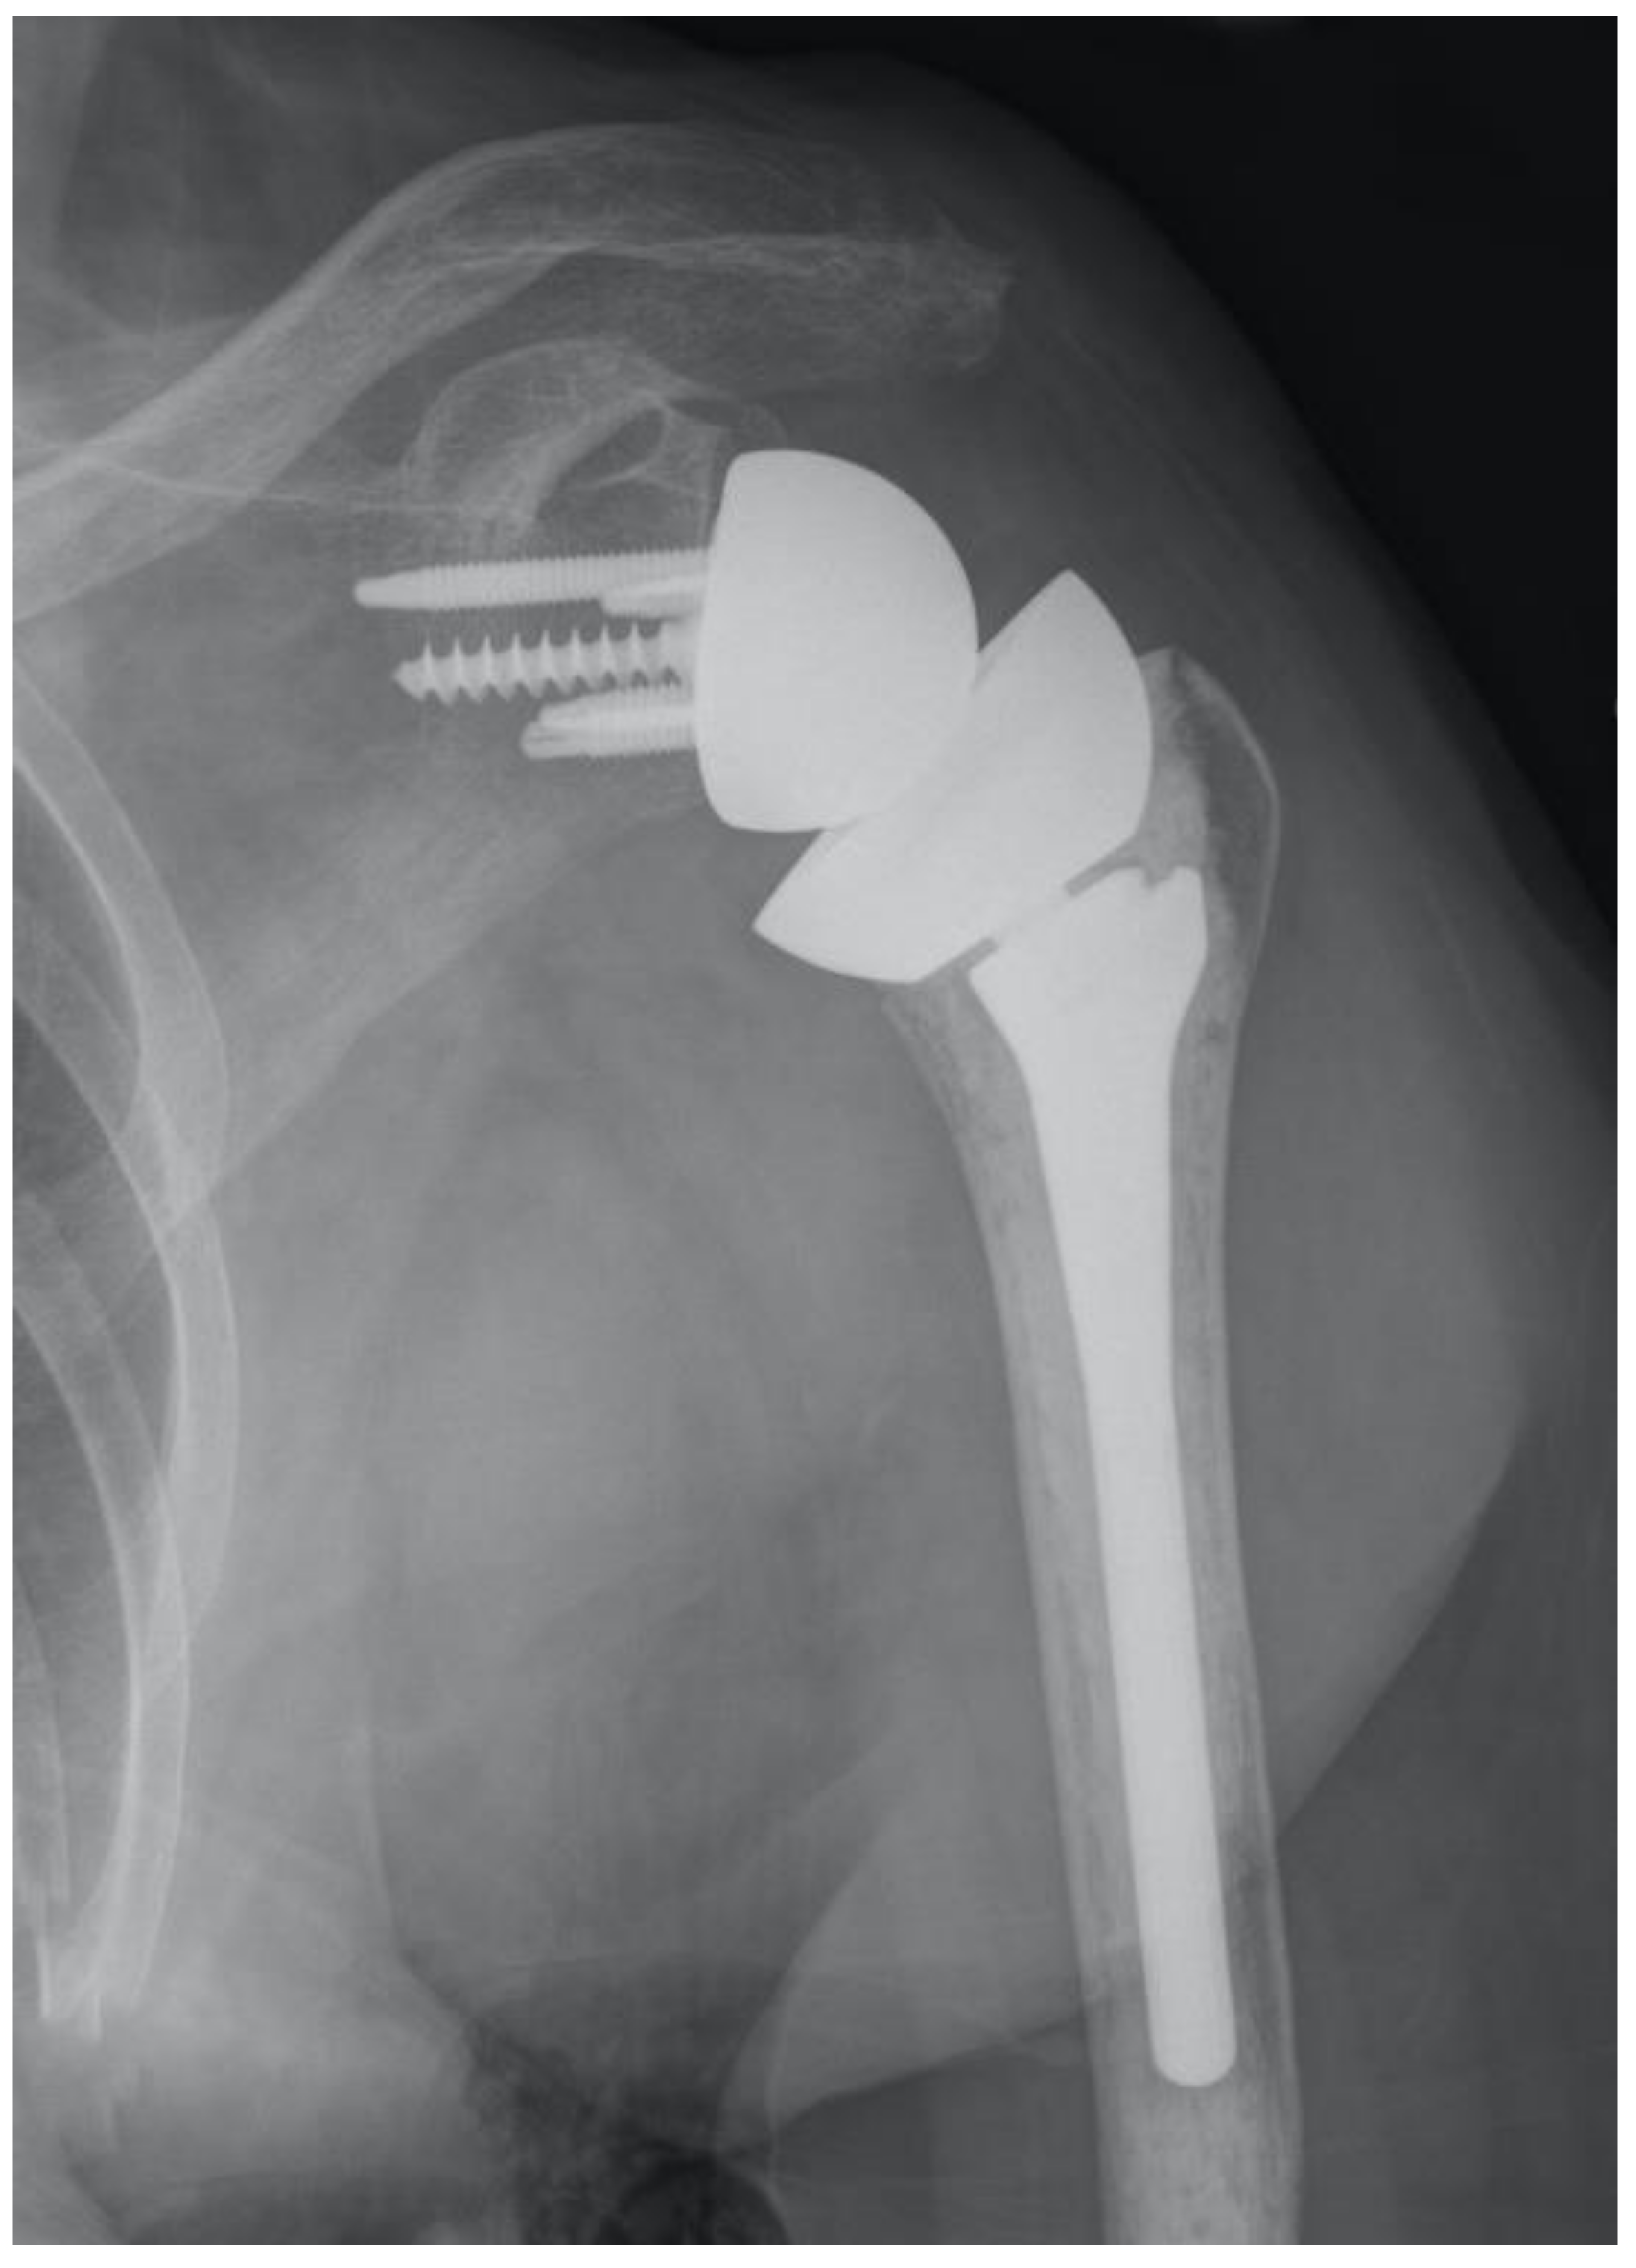

Stems that do not engage the cylindrical portion of the endosteal canal can easily be misaligned. Excessive valgus or varus will lead to a poor humeral head position in anatomic arthroplasty. Similarly, poor alignment can lead to a reverse polyethylene that is excessively horizontal with an increased risk of notching, or to a more vertical polyethylene that may facilitate dislocation. Certain short stems have been designed with just enough length to avoid malalignment [17]. Stemless prostheses are also at risk for malalignment (Figure 1). As such, care must be taken to optimize the humeral head cut to minimize the chances of malalignment with ultrashort stem and stemless prostheses.

Figure 1.

Ultrashort stems (A) and stemless prostheses (B) are at increased risk for malalignment.